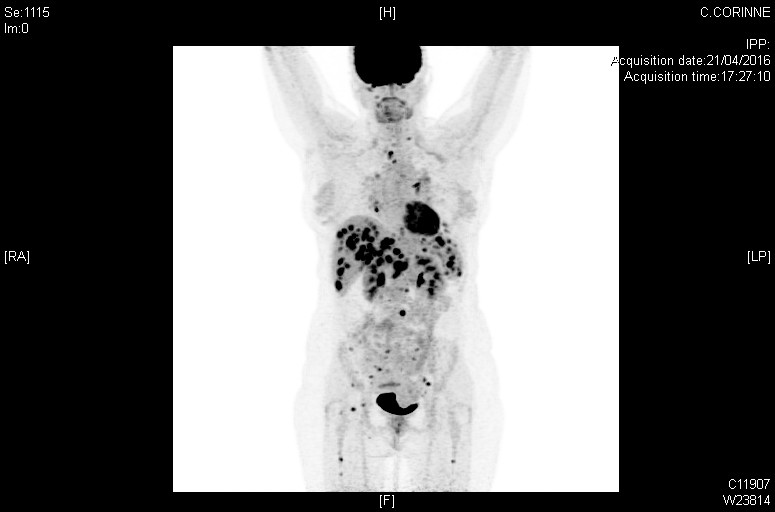

Atteintes systémiques diffuses dans le cadre d'une sarcoïdose (TEP-scan)